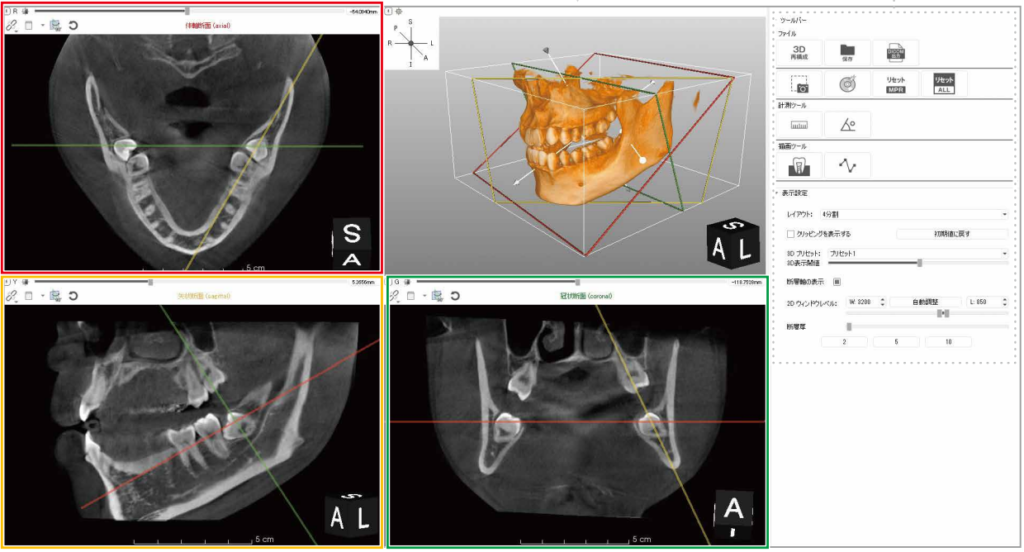

CT撮影による3D事前診断

危険な神経を正確に診断

サージカルステントとは

インプラントを入れるドリルを正確にガイドします